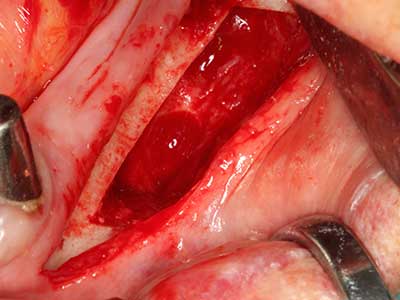

Fig. 18: Preparación de una tapa cortical con la sierra ósea piezoeléctrica (Piezomed, W&H).

Fig. 19: Zona operada después de neurolisis y eliminación del osteomo.